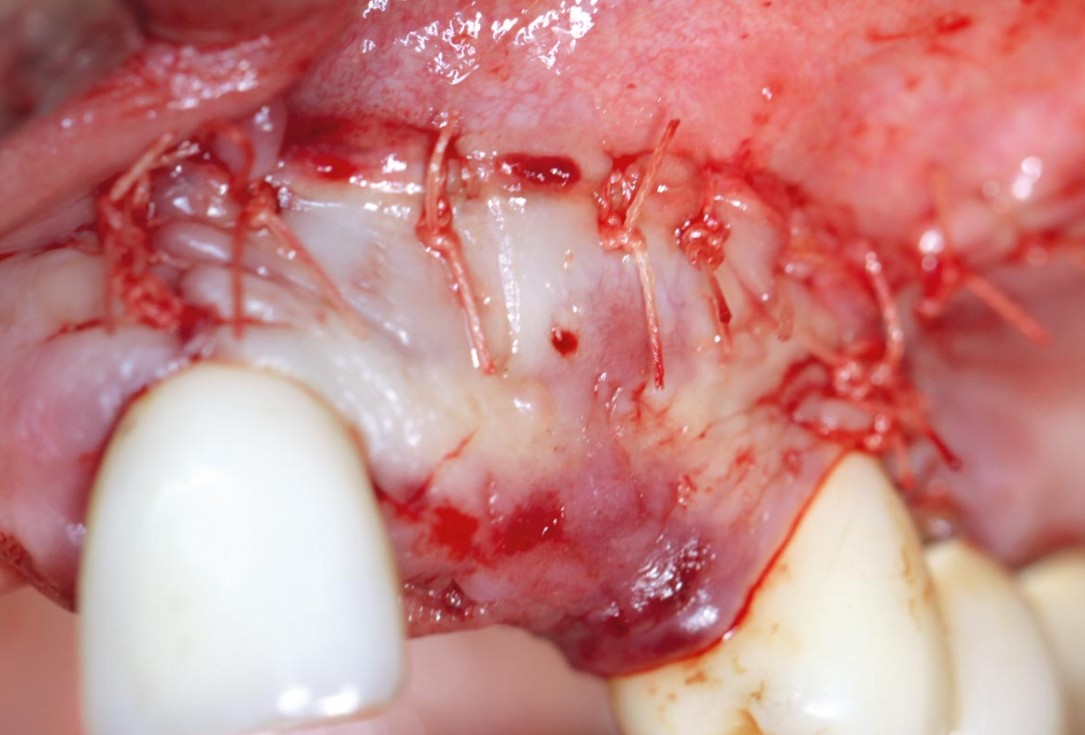

Simultaneous GBR and implantation using maxgraft® granules and autologous bone